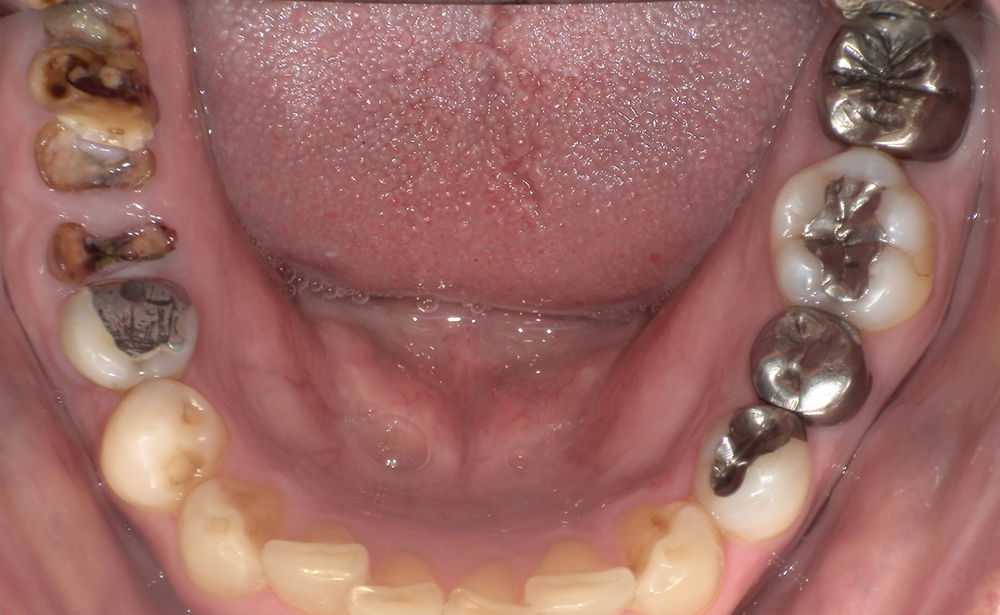

-

<治療前>

<治療後>

主訴:上の前歯が抜けてしまった、入れ歯ではうまく噛めない。

処置内容:抜歯即時 ストローマンインプラント6本埋入

費用:¥2,640,000(税込)

治療期間:3カ月

副作用・リスク:

埋入本数が多いと一時的に頬部に青痣(内出血)が生じることがありますが時間と共に消失します。